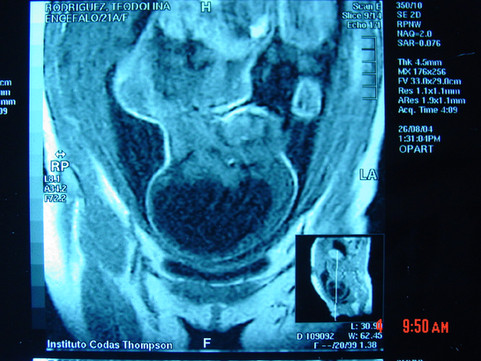

Hidrocefalia en Paraguay

Quizá sea esto el reflejo de un aumento sigiloso de la oferta de tratamiento de la hidrocefalia y otras patologías relacionadas al crecimiento cefálico (quistes, tumores, etc.) en nuestro país.

La incorporación de la Neuroendoscopía como parte del armamentario terapéutico en el país que ya data del año 2002 ha representado un punto de inflexión en cuanto a incorporación de tecnología médica en la neurocirugía nacional, siendo sin lugar a dudas la tercer ventriculostomía endoscópica TVE (se llama así el tratamiento con endoscopía de la hidrocefalia) el procedimiento más útil que se puede realizar con el neuroendoscopio.

Atribuimos, asimismo, la disminución de los casos de hidrocefalia no tratados o tratados tardíamente al crecimiento que ha tenido el sistema de salud pública en cuanto a infraestructuras hospitalarias y recursos humanos calificados y la existencia de más equipos de imágenes que permiten el diagnóstico temprano y la referencia inmediata a los centros de complejidad.